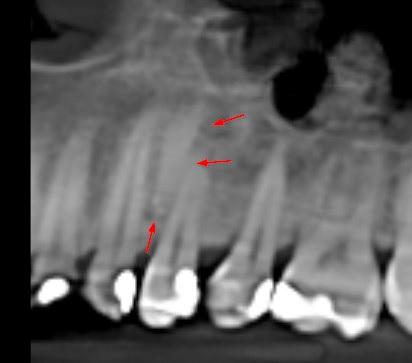

Pacjentka: wiek 34 l.

Badanie z dnia: 05.08.2023

Dane kliniczne: diag. guzów w obrębie części twarzowej czaszki -

okolica z.36 oraz kąta lewego żuchwy - w wywiadzie fibromatoza

Na podstawie obrazu radiologicznego w obrębie twarzoczaszki ukazującego liczne kostniaki, zębiaki, zaburzenia rozwojowe zębów: zęby nadliczbowe, zęby zatrzymane, mikrodoncja, zwapnienia w obrębie nosogardzieli stwierdza się jako zasadne przeprowadzenie diagnostyki w kierunku zespołu Gardnera.